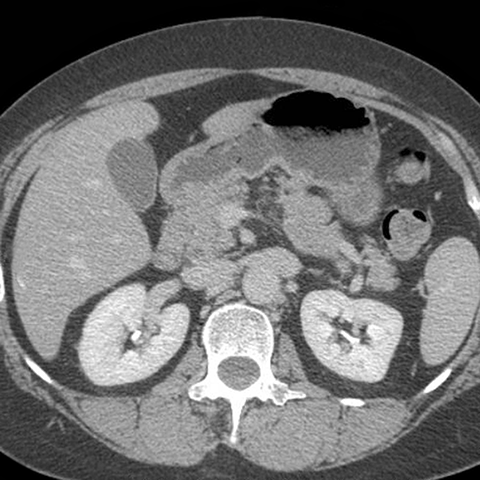

Normal Stomach, axial CT [4 of 4]